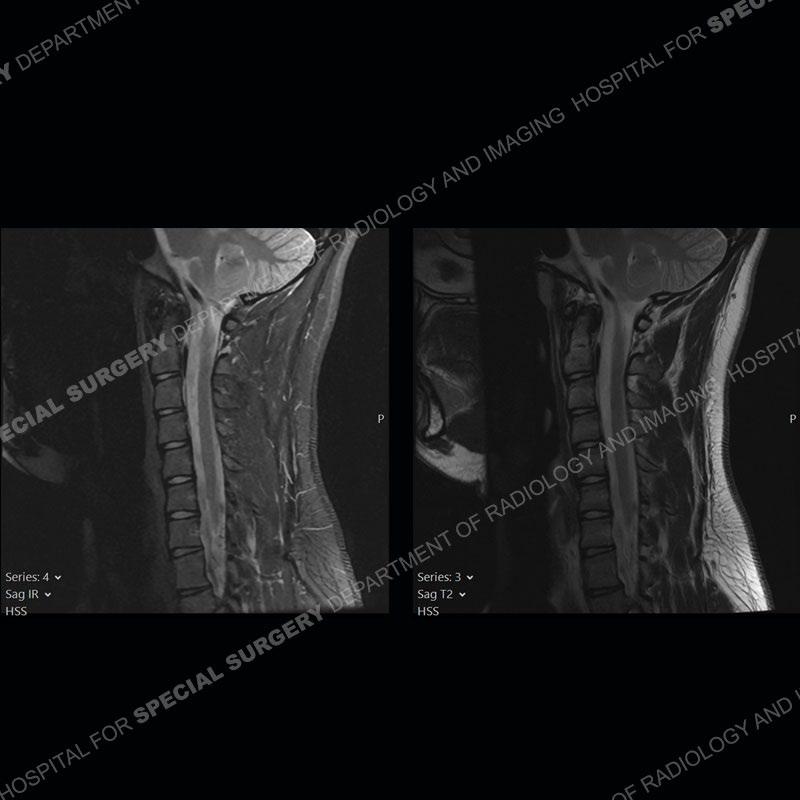

The images on the neutral sagittal images do not demonstrate any appreciable abnormality. On the flexion images, there is a forward displacement of the spinal cord centered on C6-C7. There is an expansion of the posterior dural sac which shows marked enhancement. Prominent flow voids are present of the expanded posterior dural sac on the T2 and T1 post contrast images.

Not present in this case, but frequently found is abnormal T2 signal intensity of the lower cervical cord about the area of maximum forward displacement. This can be seen on the neutral and flexed position imaging. Shown well in this case is the marked, crescentic expansion of the posterior dural sac. The sac shows marked enhancement with prominent flow voids and is often hyperintense on T1 and T2 images. The spinal cord as shown in this case is typically anteriorly displaced about the lower cervical cord.